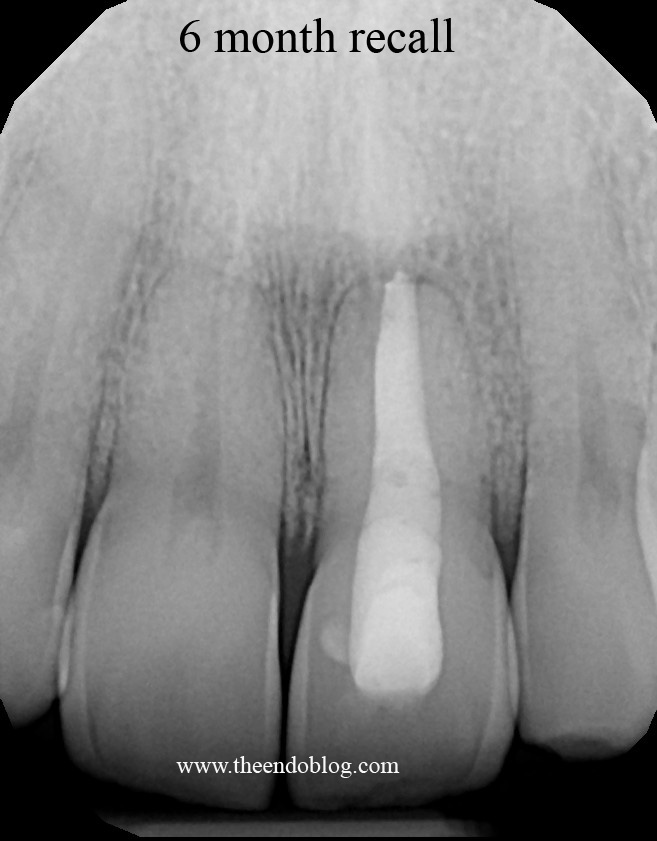

UPDATE: 6 month recall of this tooth shows complete periapical healing. Patient reports no symptoms and full function.